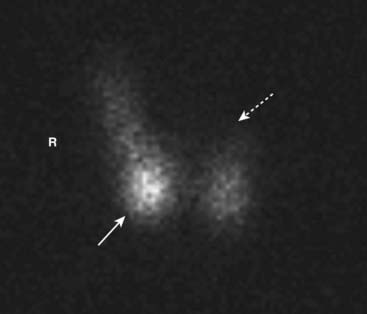

Metastatic bone disease usually presents with a pattern of multiple, asymmetric focal areas of increased uptake (“hot spots”) on bone scans. Even lytic metastases (e.g., those caused by bronchogenic carcinoma) usually produce enough osteoblastic response to be positive on a bone scan (Fig. 2).

image

Figure 2 Metastases to bone.

Metastatic bone disease usually presents with a pattern of multiple, asymmetric focal areas of increased uptake (hot spots) on bone scans (white arrows). Even lytic metastases, e.g., those caused by bronchogenic carcinoma, usually produce enough osteoblastic response to be positive on a bone scan. This patient had metastatic breast carcinoma and had diffuse skeletal metastases including the ribs, pelvis, and spine.